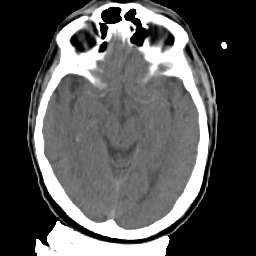

Meningioma: Roentgen-ray CT #2 -- Slice #8

[Home][Help][Clinical] Slice 8